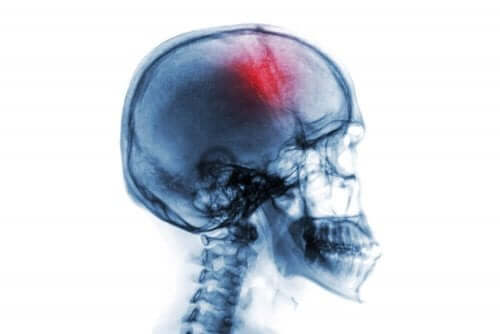

Een herseninfarct is een abrupt neurologisch syndroom met veel risicofactoren en symptomen. Het gaat om een bloeding of om verlies van de bloedcirculatie in de hersenen.

Wanneer de bloedtoevoer de hersenen niet goed bereikt, dan zal het hersenweefsel beginnen af te sterven. Dit leidt tot een neurologisch tekort, dat vervolgens kan leiden tot invaliditeit of zelfs de dood.

- Herseninfarct of beroerte. Hierbij wordt de bloedstroom naar de hersenen onderbroken. Dit wordt ook ischemische beroerte genoemd.

- Hersenbloeding. Bij deze aandoening ontstaat er een scheur of barst in een of meerdere bloedvaten in de hersenen.